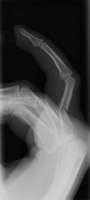

- Click on the image for a larger versionDLateral radiograph of the fourth PIP. This shows dislocation of this joint.